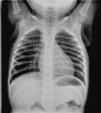

Paciente de 16 meses previamente asintomático a quien, como hallazgo casual en una radiografía de tórax realizada por fiebre, se le detecta una imagen de compresión y desviación traqueal hacia la izquierda con una hendidura en su margen derecho (fig. 1). La sombra del botón aórtico y la línea paraespinal están localizadas a la derecha, lo que sugiere que el arco aórtico es derecho.

En la radiografía de tórax, la presencia de arco aórtico derecho y una imagen de compresión traqueal son altamente sugestivas de arco aórtico doble. El diagnóstico definitivo y la evaluación del compromiso traqueal y esofágico se realizan mediante angio-TC o angio-RM4.